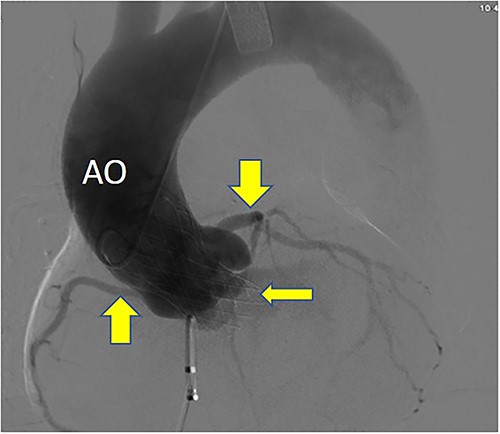

Postoperative DSA: Self-expanding valve holder’s shape and position (thin arrow) are normal, while left and right coronary artery openings (thick arrow) are unobstructed with clear blood flow.

Postoperatively, imaging studies, including TEE and digital subtraction angiography (DSA), confirmed normalization of aortic valve flow velocity and pressure gradients, with the absence of aortic regurgitation (Fig. 7). Atrial shunting disappeared, and there was no involvement of the mitral or tricuspid valves. Both the self-expanding valve prosthesis and the closure device were stably positioned, and the surgical outcome was deemed successful (Fig. 8). One month after surgery, the patient’s symptoms of chest tightness and shortness of breath had resolved.